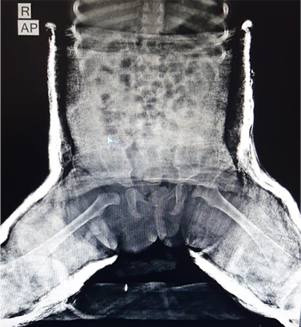

After

Post operative x-ray with hip spica showing reduced Right hip joint